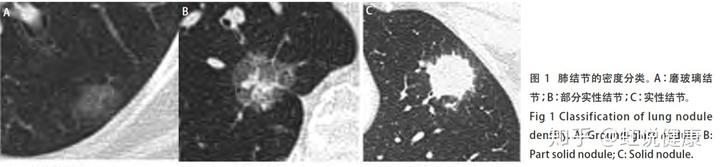

依据结节密度分类:将肺结节分为三类,其中,部分实性结节的恶性概率最高,依次为磨玻璃密度结节及实性结节。

部分实性结节(part-solid nodule)——恶性概率最高。部分实性结节是指其内既包含磨玻璃密度又包含实性软组织密度的结节,密度不均匀。

磨玻璃密度结节(groundglass nodule, GGN)——恶性概率其次。磨玻璃结节是指肺内模糊的结节影,结节密度较周围肺实质略增加,但其内血管及支气管的轮廓尚可见。

实性结节(solid nodule)——恶性概率较低。实性结节是指其内全部是软组织密度的结节,密度较均匀,其内血管及支气管影像被掩盖。